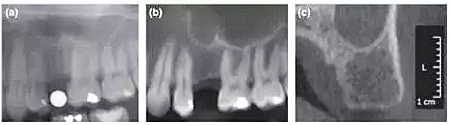

本研究共納入71名患者,所有擬種植位點(diǎn)行數(shù)字化全景(D-PAN)及錐束CT(CBCT)檢查。攝全景片時(shí),將一直徑5 mm的金屬球置于缺牙區(qū)。重組CBCT數(shù)據(jù)組分別構(gòu)建10 mm層厚的CBCT全景圖像(CBCT-pan)及1 mm層厚的斷面影像(CBCT-cross)。三名測(cè)量者在顯示器上應(yīng)用專業(yè)軟件測(cè)量圖像,在擬種植位點(diǎn)放置4個(gè)參考點(diǎn)以模擬種植體外形。分析比較根據(jù)3種影像選擇的種植體長(zhǎng)度和直徑的差異。并且針對(duì)每種種植系統(tǒng),比較根據(jù)CBCT-cross與其他2種方式(D-PAN和CBCT-pan)選擇的種植體尺寸。

結(jié)果顯示,根據(jù)CBCT-cross選擇的種植體(3個(gè)觀察者取平均值)比D-PAN和CBCTpan選擇的種植體直徑更小。在前磨牙區(qū)域,D-PAN和CBCT-pan選擇的種植體直徑也有顯著差異。相比D-PAN,CBCT-cross選擇的種植體顯著更短。在前磨牙位點(diǎn),3種測(cè)量方式選擇的種植體長(zhǎng)度無顯著差異。CBCT-cross選擇的種植體尺寸級(jí)別相比D-PAN和CBCT-pan無顯著差異。

總結(jié)來說,本研究的結(jié)果表明利用CBCT重建全景片與CBCT斷層影像選擇的種植體尺寸存在差異。在大多數(shù)病例中,相比全景片或CBCT重建全景片,根據(jù)CBCT斷層影像測(cè)量并選擇的種植體直徑和長(zhǎng)度均更小。